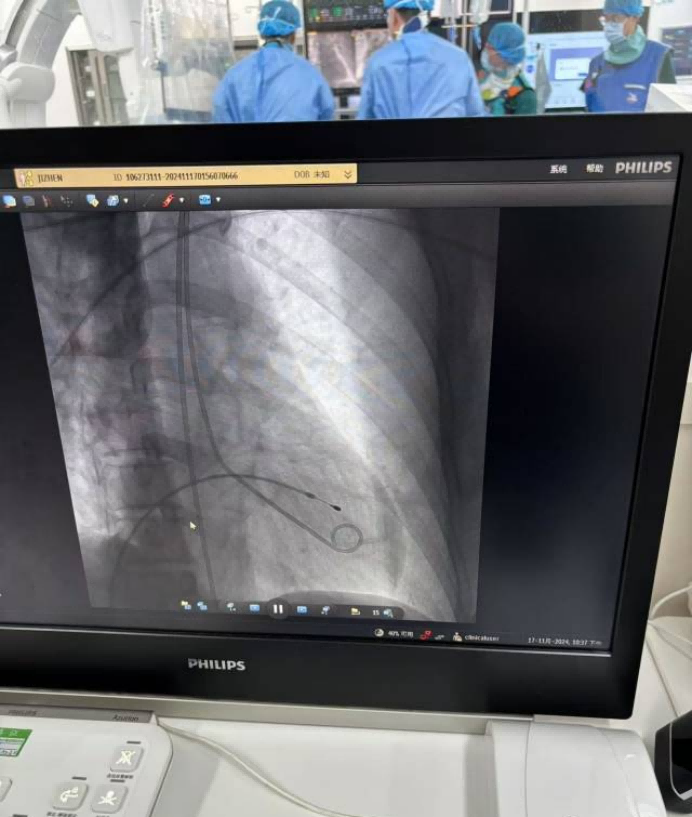

[技术亮点]: 多学科急诊联动机制、床旁快速心肌酶检测、临时起搏器紧急植入、IABP(主动脉内球囊反搏)精准应用

[治疗过程]:暴发性心肌炎症状不典型,早期诊断困难;病情发展迅速,短时间内出现多种严重并发症,治疗需迅速且精准,对医疗团队的综合能力要求极高。在患者病情危急的情况下,多学科迅速协作,精准运用先进设备稳定患者病情,避免使用更为复杂的 ECMO,成功挽救患者生命,体现了高效、精准的救治策略。

[治疗效果]:成功植入临时起搏器和启用 IABP,患者血压逐渐稳定,心律失常得到控制;经过一周诊治,临时起搏器和 IABP 安全撤除;数日后复查心脏功能明显改善,可完全下地自由活动。